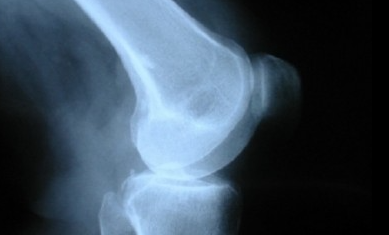

콜라겐은 관절을 보호하는 고무 같은 조직인 연골의 무결성을 유지하는데 도움이 됩니다. 나이가 들어감에 따라 체내 콜라겐 양이 감소함에 따라 골관절염과 같은 퇴행성 관절 질환의 위험이 증가합니다.

일부 연구에서는 콜라겐 보충제가 골관절염의 증상을 개선하고 전반적인 관절 통증을 줄이는데 도움이 될 수 있다고 말합니다. 골관절염이 있는 500명 이상의 사람들을 대상으로 한 5건의 연구를 검토한 결과, 평균 24주 동안 매일 약 10g의 콜라겐을 섭취하면 관절 경직과 자가 보고한 관절 통증이 크게 개선되는 것으로 나타났습니다.

콜라겐 효능 3. 뼈 손실 예방

뼈는 대부분 콜라겐으로 만들어져 구조와 강도를 제공합니다. 신체의 콜라겐이 나이가 들면서 퇴화하는 것처럼 골량도 감소합니다. 이것은 낮은 골밀도와 높은 골절 위험을 특징으로 하는 골다공증과 같은 상태로 이어질 수 있습니다.

연구에 따르면 콜라겐 보충제는 골다공증으로 이어지는 뼈 파괴를 억제하는데 도움이 될 수 있습니다.

12개월간의 연구에서 여성들은 매일 5g의 콜라겐이 포함된 칼슘 보충제 또는 콜라겐이 없는 칼슘 보충제를 섭취했습니다. 연구 끝에 칼슘과 콜라겐 보충제를 섭취한 사람들은 칼슘만 섭취한 사람들보다 뼈 파괴를 촉진하는 단백질의 혈중 농도가 현저히 낮았습니다.